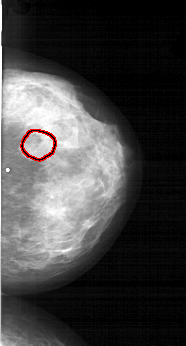

FILE: A_1566_1.RIGHT_CC.OVERLAY

TOTAL_ABNORMALITIES 1

ABNORMALITY 1

LESION_TYPE MASS SHAPE LOBULATED MARGINS OBSCURED

ASSESSMENT 4

SUBTLETY 3

PATHOLOGY BENIGN

TOTAL_OUTLINES 1

BOUNDARY